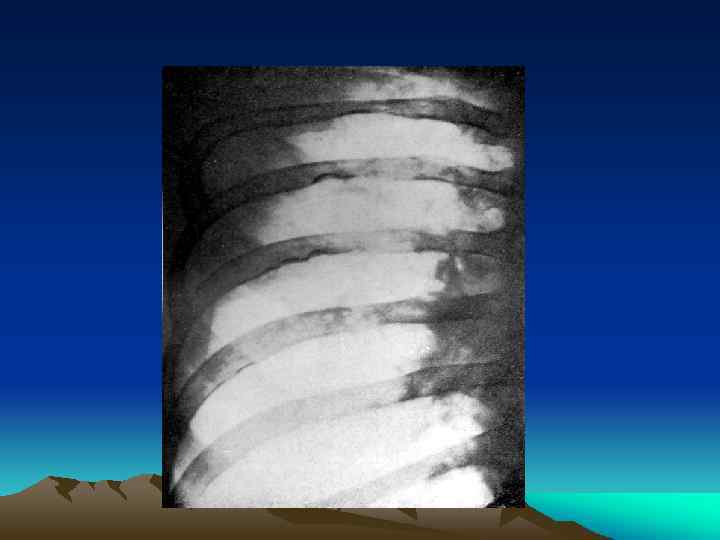

Коарктация аорты Синдром Кушинга Преимущественно повышено САД на руках и снижено АД на ногах. Аускультативно – систолический шум типа изгнания. При пальпации бедренной артерии одновременно с лучевой артерией отмечается задержка пульсации на бедренной. На Ro-гр. – узуры ребер. Коарктацию можно визуализировать с помощью УЗИ, но окончательно – при аортографии. Причина–повышенная секреция кортизола, или близких кортикостероидов. Клиника– круглое, полнокровное, «лунообразное» лицо, ожирение, гипертензия, остеопороз, аменоррея, гирсутизм. Никогда не бывает гипогликемии. В 85% случаев бывает СД. Диагностика основана на выявлении гиперкортицизма. Информативным является исс- 17 ОКС (не менее 25 -28 ммоль в сутки). .